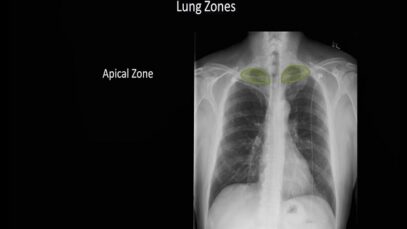

computed tomography of the chest Computed tomography (CT) is an imaging technique that has revolutionized medical imaging. It is widely available, fast, and provides a detailed view of the internal organs and structures. Helical CT is most common, but conventional, axial, step-and-shoot CT is used for thin section high-resolution CT scanning of the lungs, coronary […]